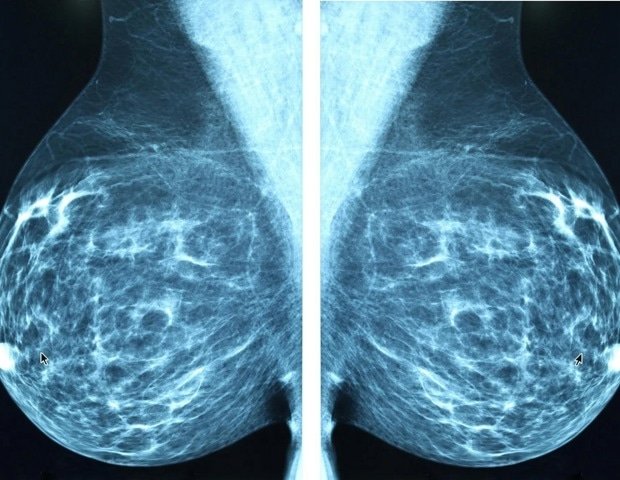

A study led by Weill Cornell Medicine and NewYork-Presbyterian researchers has found that mysterious circulating tumor cells called double-positive (DP) cells are associated with shorter survival times in patients with advanced breast cancer. This finding highlights the potential importance of these poorly studied cells in breast cancer progression.

Circulating tumor cells are shed tumor cells that can give rise to secondary tumors (metastasis) and are commonly found in the blood of cancer patients. Dual-positive cells are circulating cells that carry markers of both tumor and immune cells and are thought to be hybrid cells resulting from rare fusions of tumor and immune cells. Recent studies have linked the presence of DP cells in a patient’s blood to worse outcomes in melanoma and pancreatic cancer.

In a new study published March 11 in the journal Science Translational Medicine, researchers found that DP cells are associated with shorter survival times in patients with advanced breast cancer, particularly in the aggressive “triple-negative” breast cancer subtype. The research team also showed in animal models that DP cells can seed breast cancer metastases.

The researchers initially analyzed blood samples from 340 women with advanced breast cancer who agreed to participate when the study began at Northwestern University, Dr. Cristofanilli’s hometown. DP cells tended to be fewer in number than normal circulating tumor cells, which are known risk factors for metastasis and shortened survival. However, the researchers identified at least one DP cell in 152 (44.7%) women. Median survival for patients with three or more detected DP cells was only 23.5 months, compared to 33.6 months for patients with fewer than three detected DP cells. The association between more than three DP cells and shorter median survival was tested in an additional group of 51 patients with advanced breast cancer who agreed to participate in the study at Dr. Cristofanilli’s clinic at NewYork-Presbyterian/Weill Cornell Medical Center.

A comparison of different breast cancer subtypes showed that the risk of shortened survival with DP cells was mainly concentrated in triple-negative breast cancer patients. This is a subtype in which tumor cells lack the three most common breast cancer markers: estrogen, progesterone, and HER2 receptors.